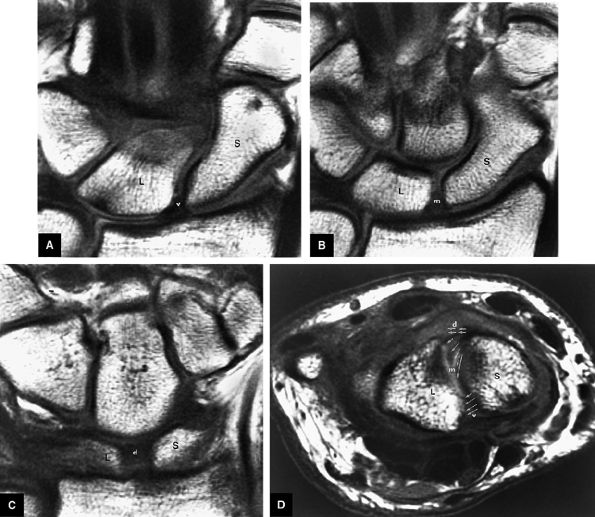

FIGURE 10.73 ● Anatomy of the scapholunate ligament complex on three separate coronal images. (A) Volar component. (B) Membranous component. (C) Dorsal component. (D) On a corresponding axial image all three components of the scapholunate ligament complex are demonstrated. The dorsal scapholunate ligament is horizontally oriented and is perpendicular to the joint. The fibers of the membranous portion of the scapholunate ligament course peripherally and obliquely from the scaphoid downward toward the lunate in a dorsal-to-volar direction. The volar scapholunate ligament courses obliquely from the scaphoid downward to the lunate. This arrangement of scapholunate ligament fibers biomechanically hinges the joint dorsally at the level of the dorsal transverse fibers. In forced extension, scapholunate ligament failure initiates in its volar aspect. S, scaphoid; L, lunate; v, volar component; m, membranous component; d, dorsal component. Arrows correspond to the course of each component of the scapholunate ligament.